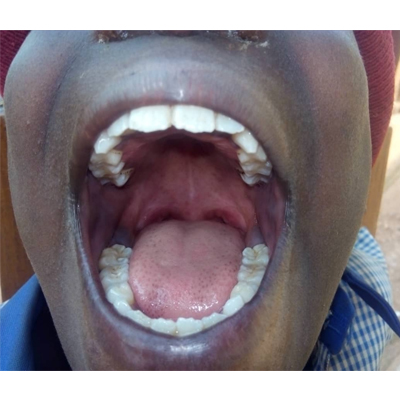

Oral Health Solutions Organization (OHSO), founded in October 2019, is an active non-governmental organisation (NGO) at the forefront of improving oral health in Rwanda, through oral health promotion, oral disease prevention and advocacy. The NGO vies to complement adequately Government effort to promote health and prevent diseases through school and maternal health settings. We adopt proactive engagement across all platforms in working alongside various government ministries, institutions,NGOs,dental professionals and the public.